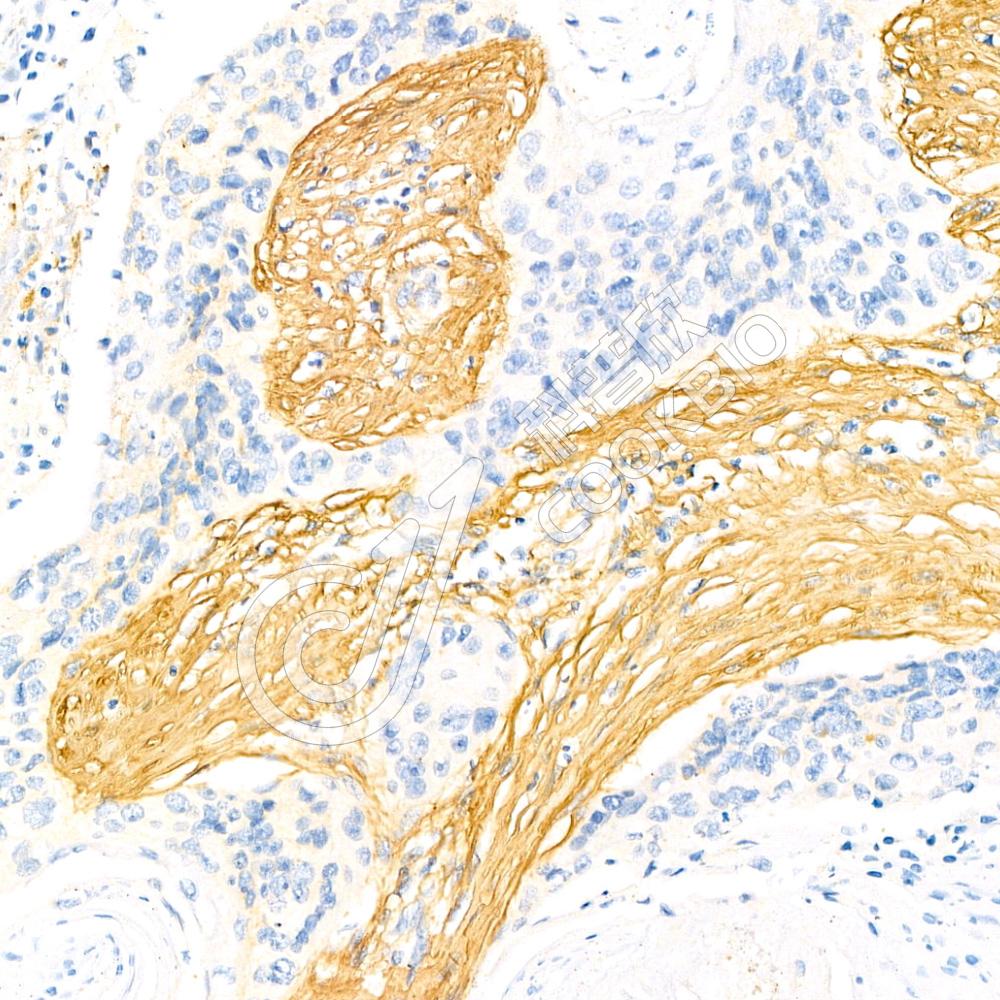

IHC检测Collagen II蛋白(货号 K236063).

样品: 小鼠骨, 4%多聚甲醛 (货号KSG1101) 固定12-24小时.

抗原修复: 柠檬酸抗原修复液(干粉, pH 6.0) (KSG1201), 98℃, 20分钟.

—抗: 1: 1600稀释, 4℃ 孵育过夜.

二抗: S-vision免疫组化多聚二抗(山羊抗小鼠), 即用型(货号KB3903), 室温孵育20分钟.

样品: 大鼠骨, 4%多聚甲醛 (货号KSG1101) 固定12-24小时.